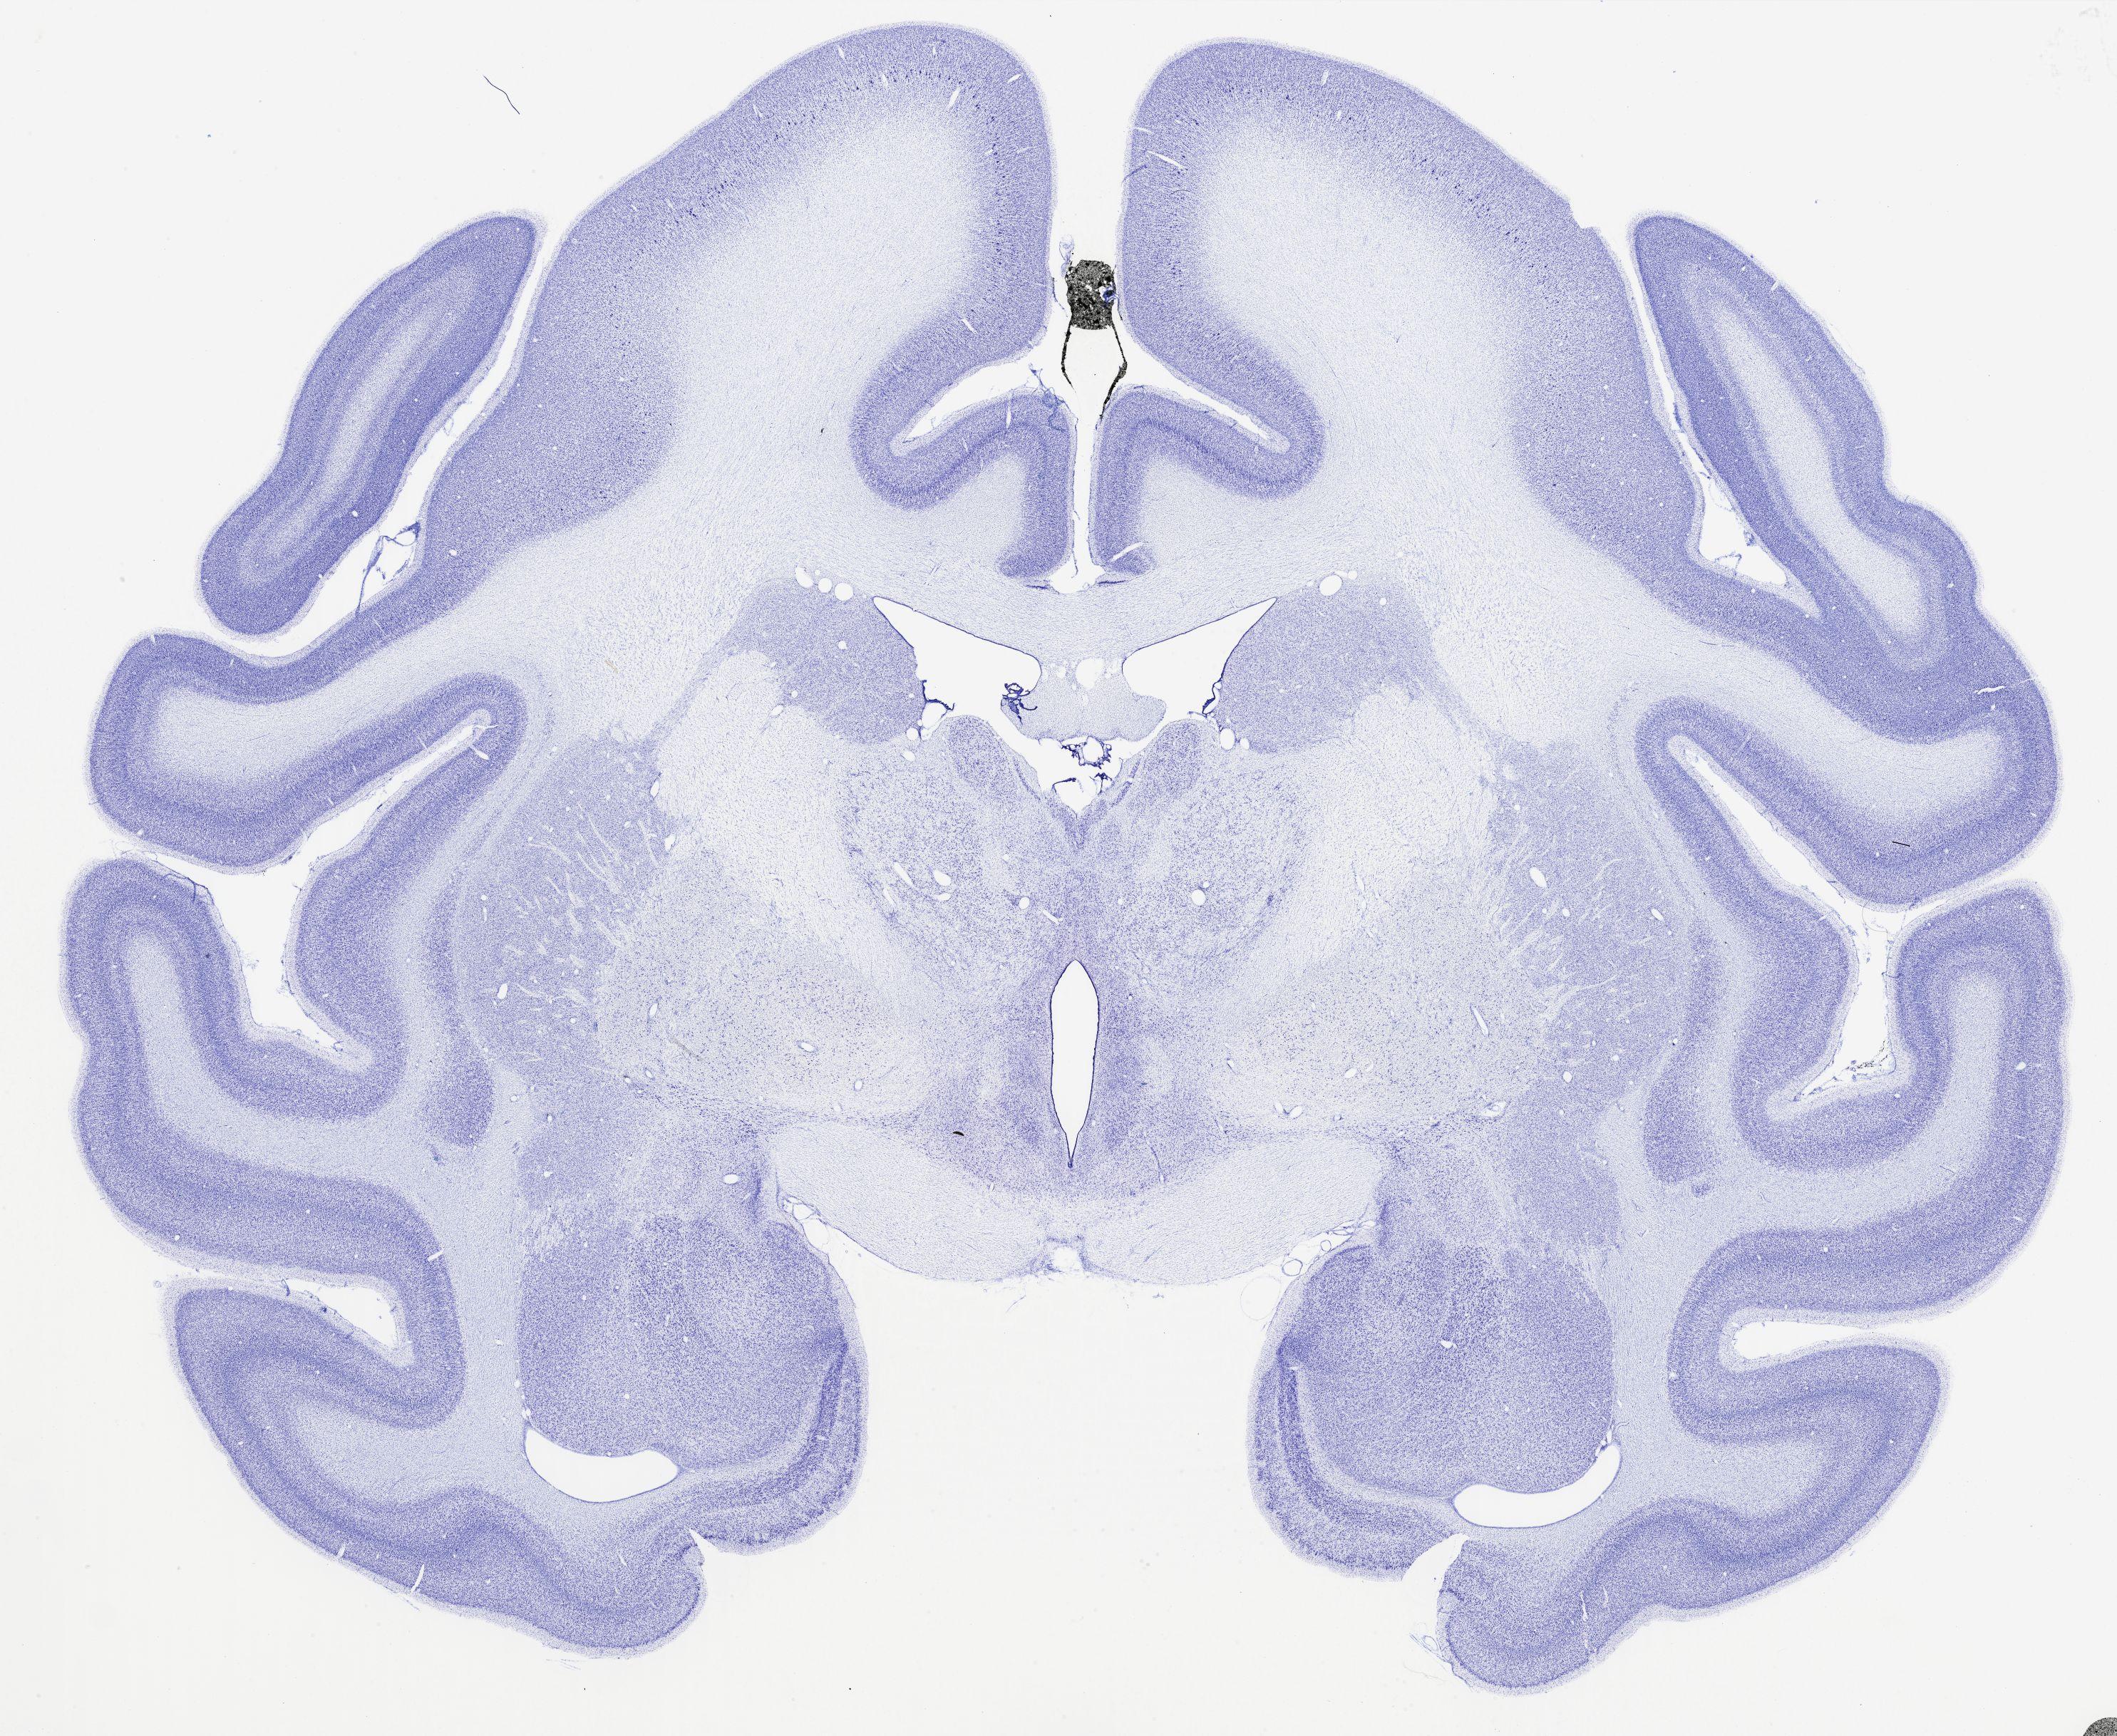

thumbnail

321